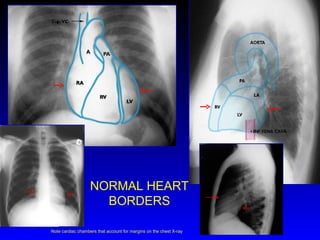

NORMAL HEART BORDERS Note cardiac chambers that account for margins on the chest X-ray

R Atrium R Ventricle 3.  Apex of L Ventricle Superior Vena Cava Inferior Vena Cava 6.  Tricuspid Valve Pulmonary Valve Pulmonary Trunk 9.  R PA  10.  L  PA

• #6 Note cardiac chambers that account for margins on the chest X-ray